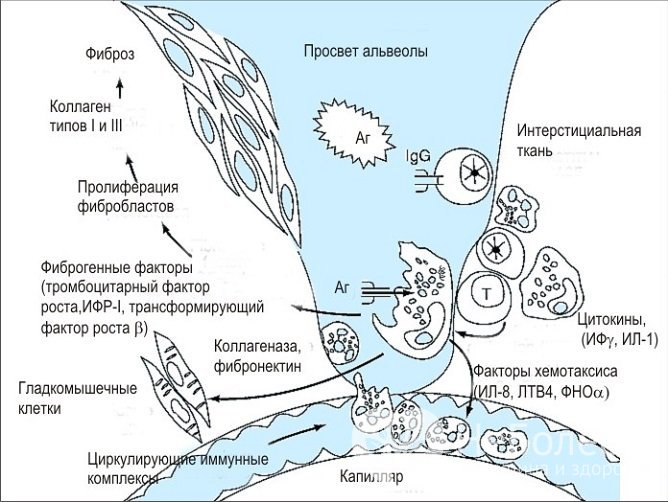

Патогенез идиопатического фиброзирующего альвеолита

Патогенез идиопатического фиброзирующего альвеолитаСтадии заболевания

В соответствии с особенностями воспалительного процесса выделяются три стадии идиопатического фиброзирующего альвеолита:

- Острая. Наблюдается поражение эпителия и альвеолярных капилляров, формируются гиалиново-мембранные образования, не позволяющие свободно расширяться ткани альвеол в процессе вдоха.

- Хроническая. В альвеолах откладывается коллаген, происходит замещение интерстициальной ткани фиброзной.

- Терминальная. Фиброзная ткань практически полностью замещает ткань альвеол и капилляров. В легких возникают множественные полостные образования, в результате чего они напоминают пчелиные соты. Значительно нарушается газообмен, нарастает дыхательная недостаточность, что в конечном итоге приводит к гибели пациента.